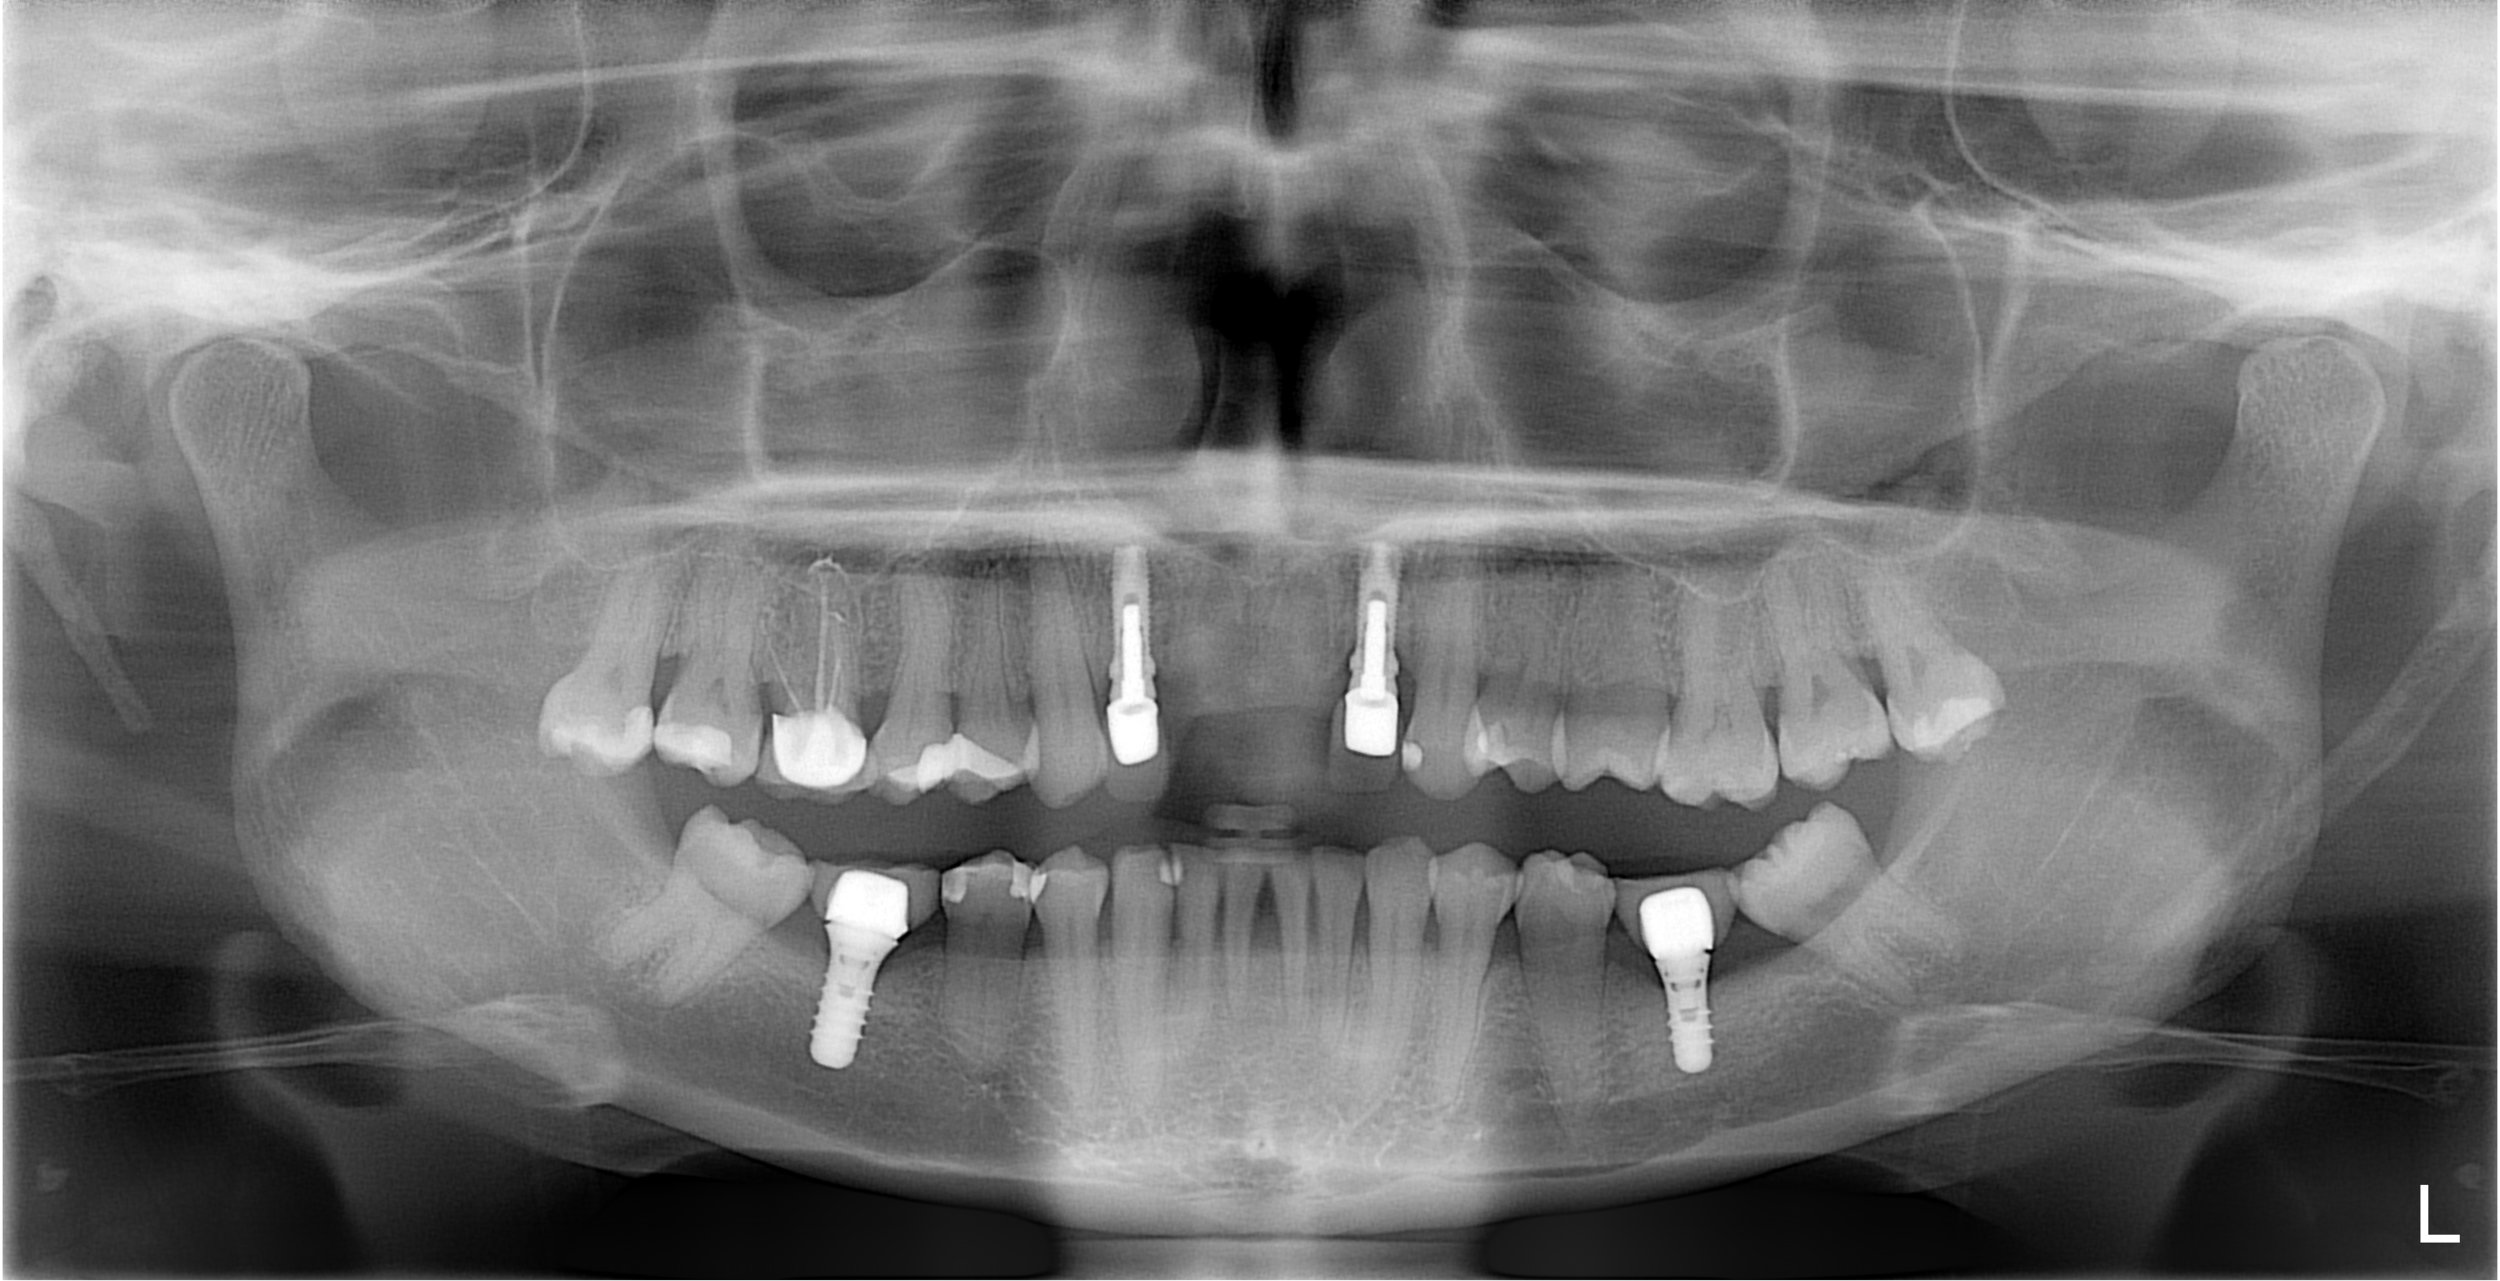

Pre X-Ray

Before